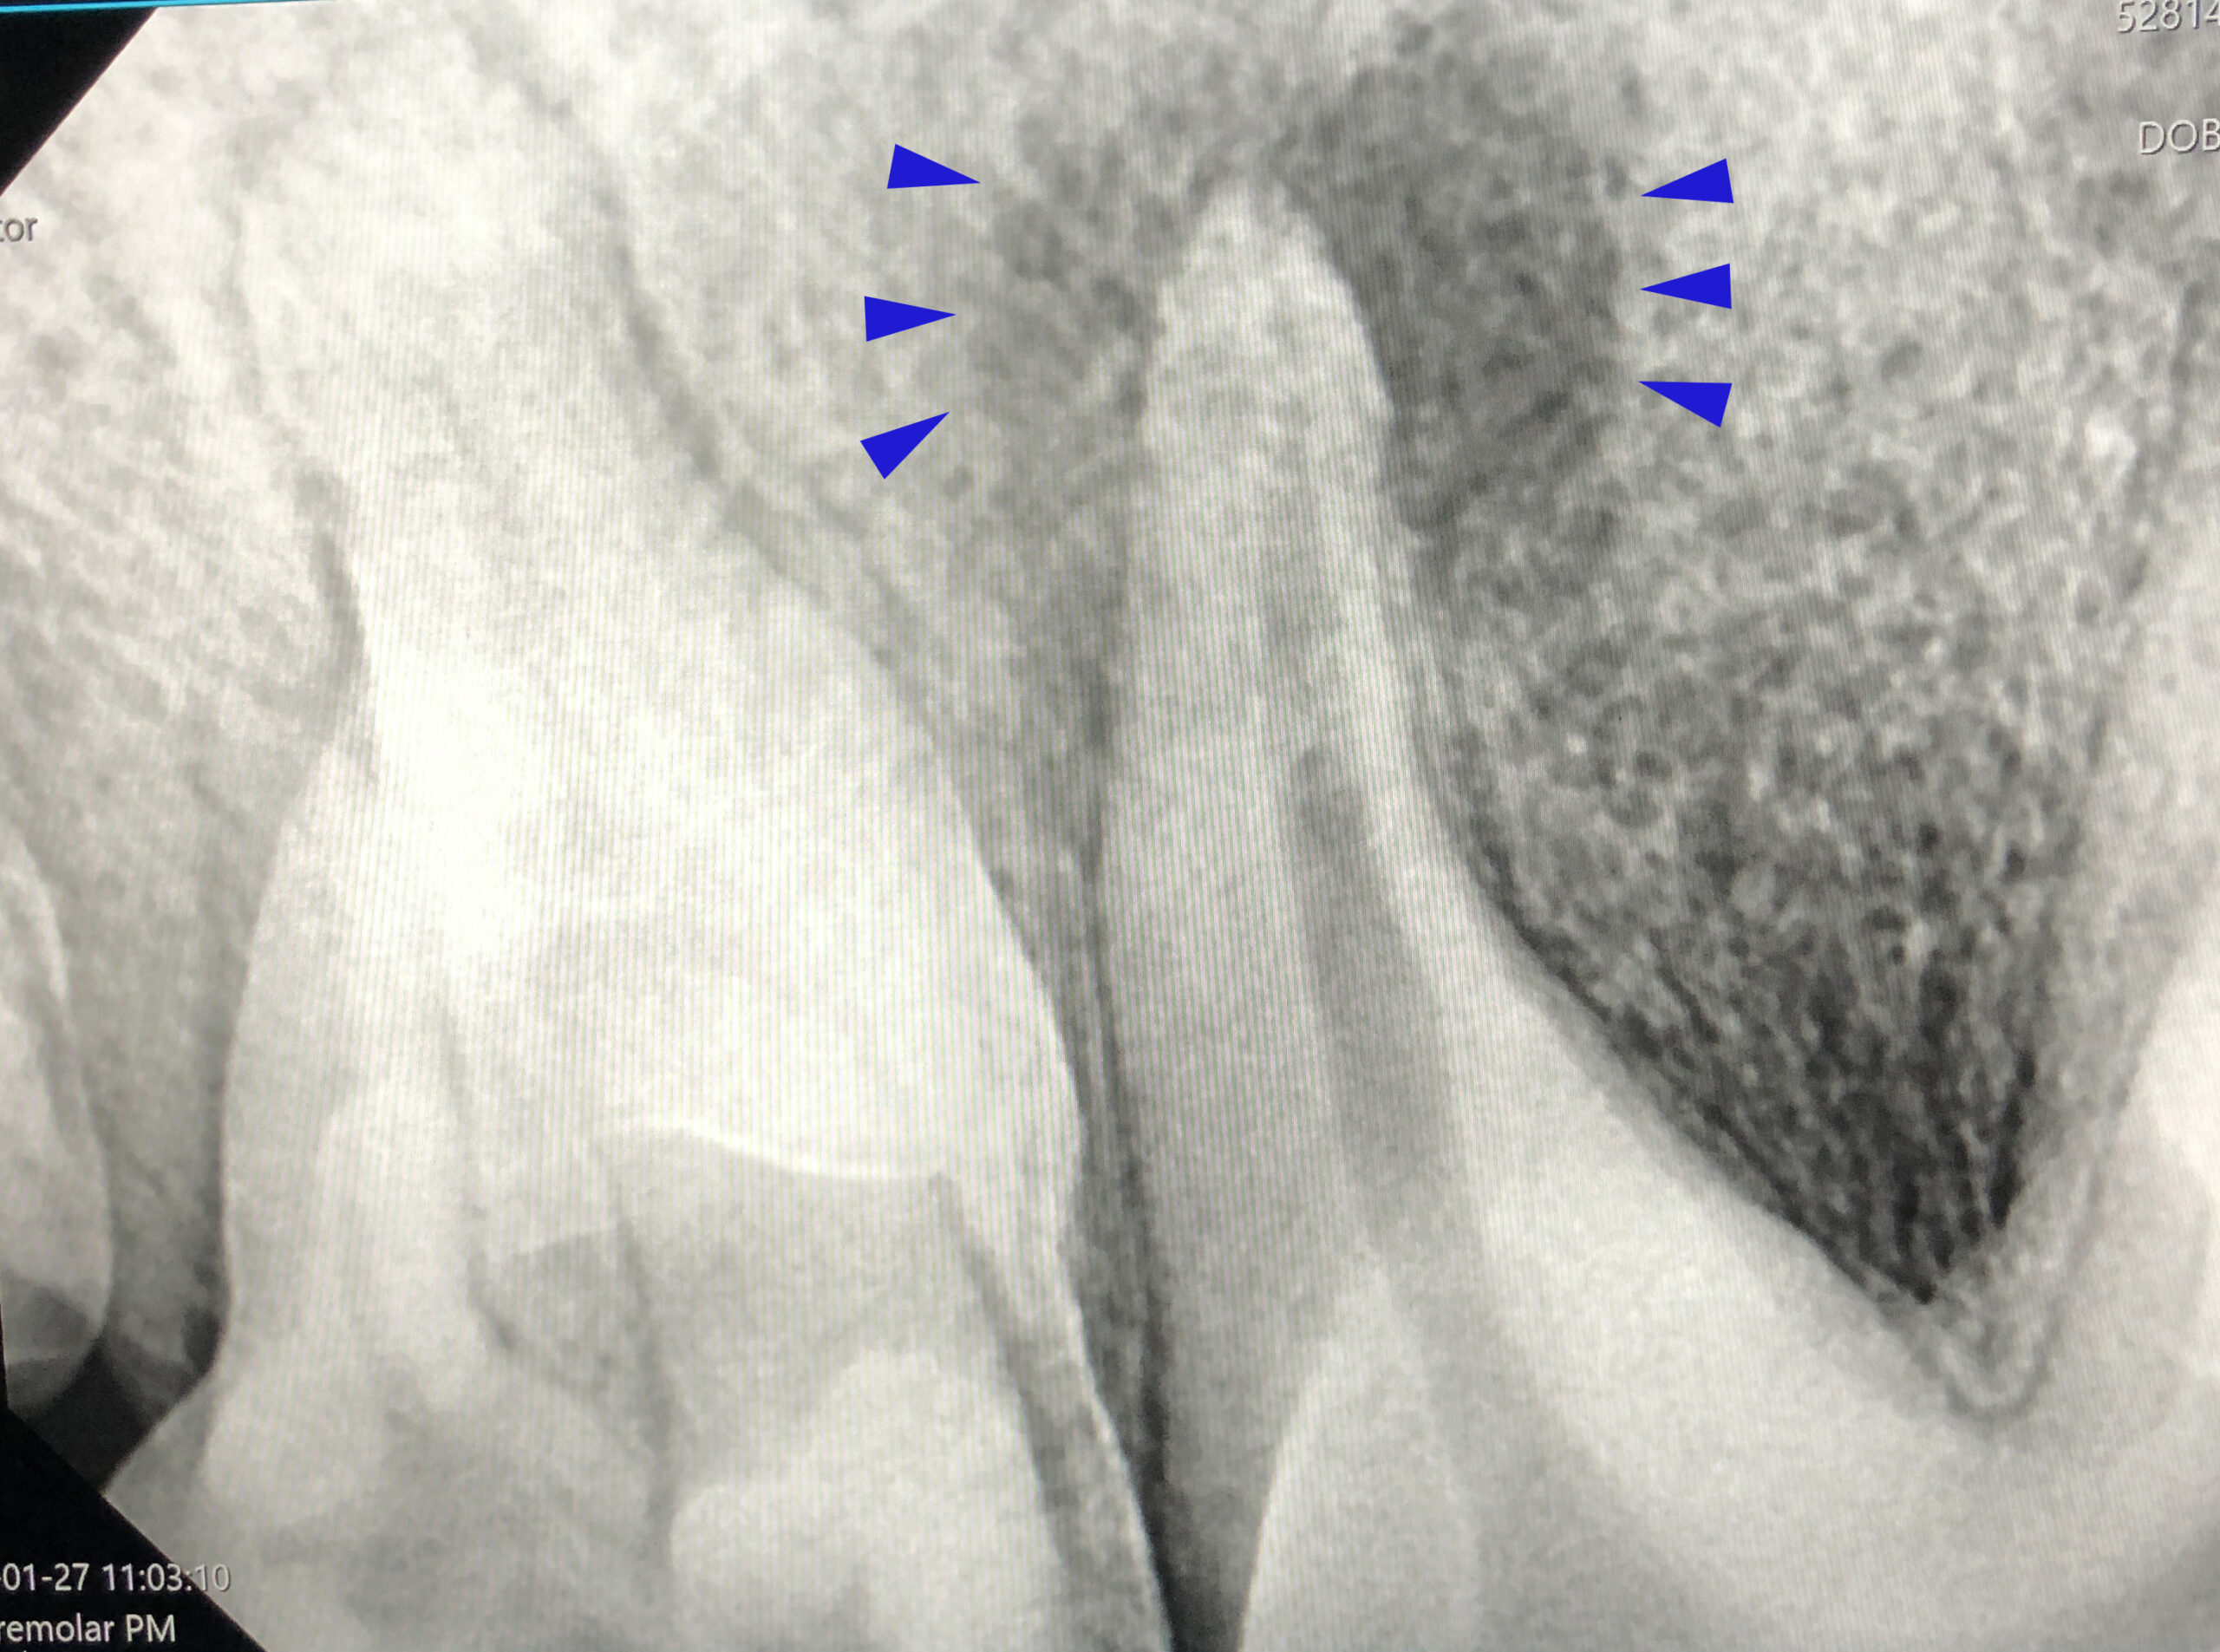

Onze praktijk beschikt over al deze onderdelen. Ons dentale röntgenapparaat is speciaal geschikt om kleine onderdelen op de foto te zetten. Tijdens gebitsbehandelingen kunnen we hiermee onder het tandvlees verstopte wortels van tanden en kiezen in beeld brengen, zodat gerichter besloten kan worden of een extractie nodig is. De foto kan goed laten zien of er een glazuuraantasting aanwezig is, of er wortels ontbreken of dat deze juist vergroeid zijn met het tandbeen. Vooral dit laatste probleem zorgt voor een lastigere extractie. Als je van tevoren weet dat de wortel vergroeid is met het tandbeen, wordt de extractie op een andere manier uitgevoerd.

Bij katten kunnen met digitale röntgen problemen goed bekeken worden. Bij hen bestaat de aandoening Feline Odontoclastic Resorptive Lesions, waarbij er oplossing ontstaat van delen van de tanden en kiezen net onder het tandvlees. Bij een routine-check is dit moeilijk zichtbaar. Vaak zie je alleen wat irritatie van het tandvlees. Op de röntgenfoto zie je echter duidelijk een oplossing van de wortel. Hierbij wordt ook zichtbaar of er van het restantje kies dat je uit de kaak haalt nog een wortelpuntje in de kaak aanwezig is.